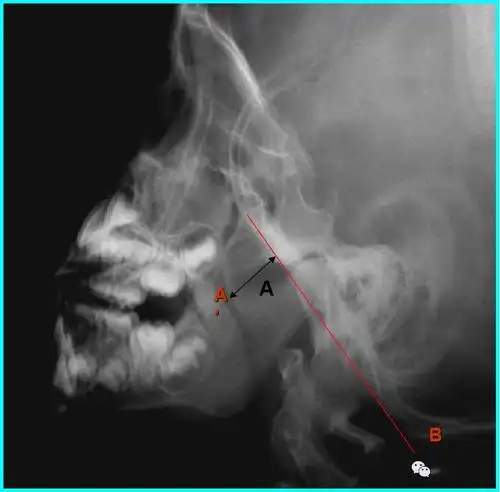

鼻咽侧位片的测量方法(二)